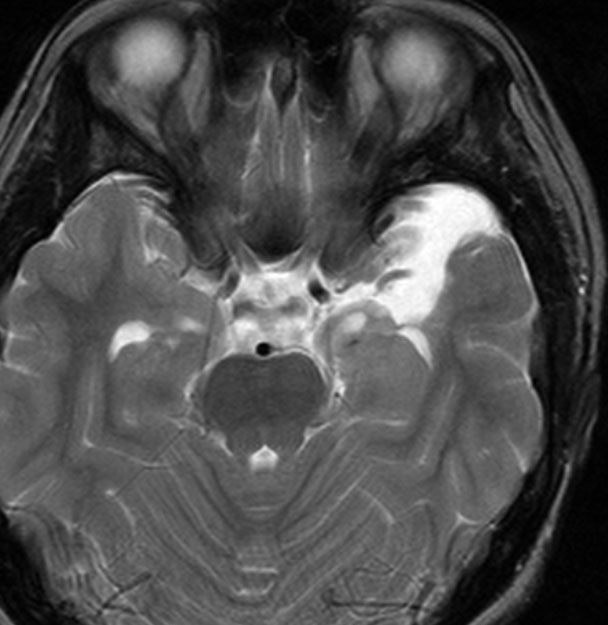

脳幹部から発生した退形成性神経節膠腫 grade 3

軽い右顔面神経麻痺で発症した小児で,右上下肢の軽度の失調症もありました。脳幹部(橋)の右背側から発生した腫瘍で,軽度の閉塞性水頭症を合併しています。左はT2強調画像で,橋の右側ににじむような浸潤像と浮腫があります。腫瘍は小嚢胞を形成してT2強調画像で実質は等信号です。真ん中の画像はCISS画像で橋が腫大しているのがよくわかります。右側はガドリニウム増強像で,全体が増強されてまだらな増強所見となっています。正中後頭下開頭で全摘出 gross total removal して,局所放射線治療とtemozolomide, cisplatine, etoposide, gleevec, hydoreaなどの化学療法を行いましたが,手術後4ヶ月で激しい播種再発を来しました。